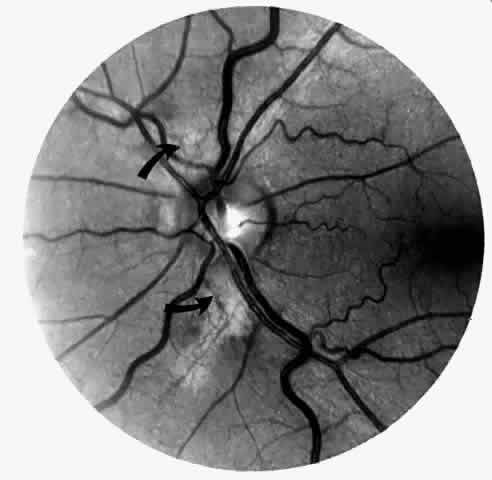

Transient dark red spots (similar to conjunctival commas), representing plugs of sickled erythrocytes within superficial capillaries, may be seen on the surface of the optic disc (Fig. 3 and Color Plate 1A). These disc changes are not associated with any functional or anatomic abnormalities. They are found in 11% of all patients with sickle cell disease, but appear to be more common in patients with homozygous sickle cell anemia, occurring in 29% of these patients.67 The disc sign correlates with the presence of conjunctival commas and ISCs.

Fig. 3. Disc sign showing dilated loops (arrow) and multiple comma-shaped vascular segments.